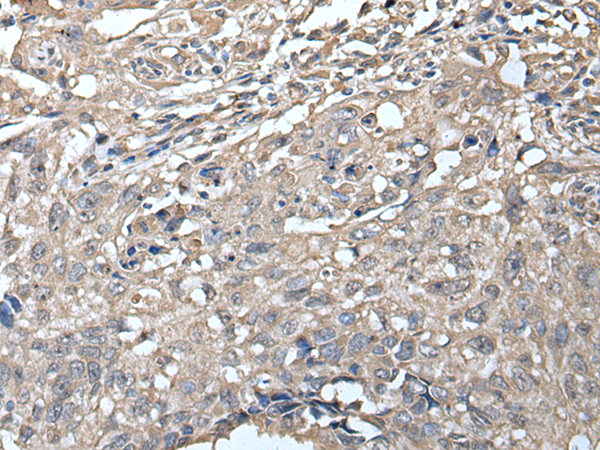

IHC positive control:

|

Human thyroid cancer

IHC Recommend dilution:

20-100